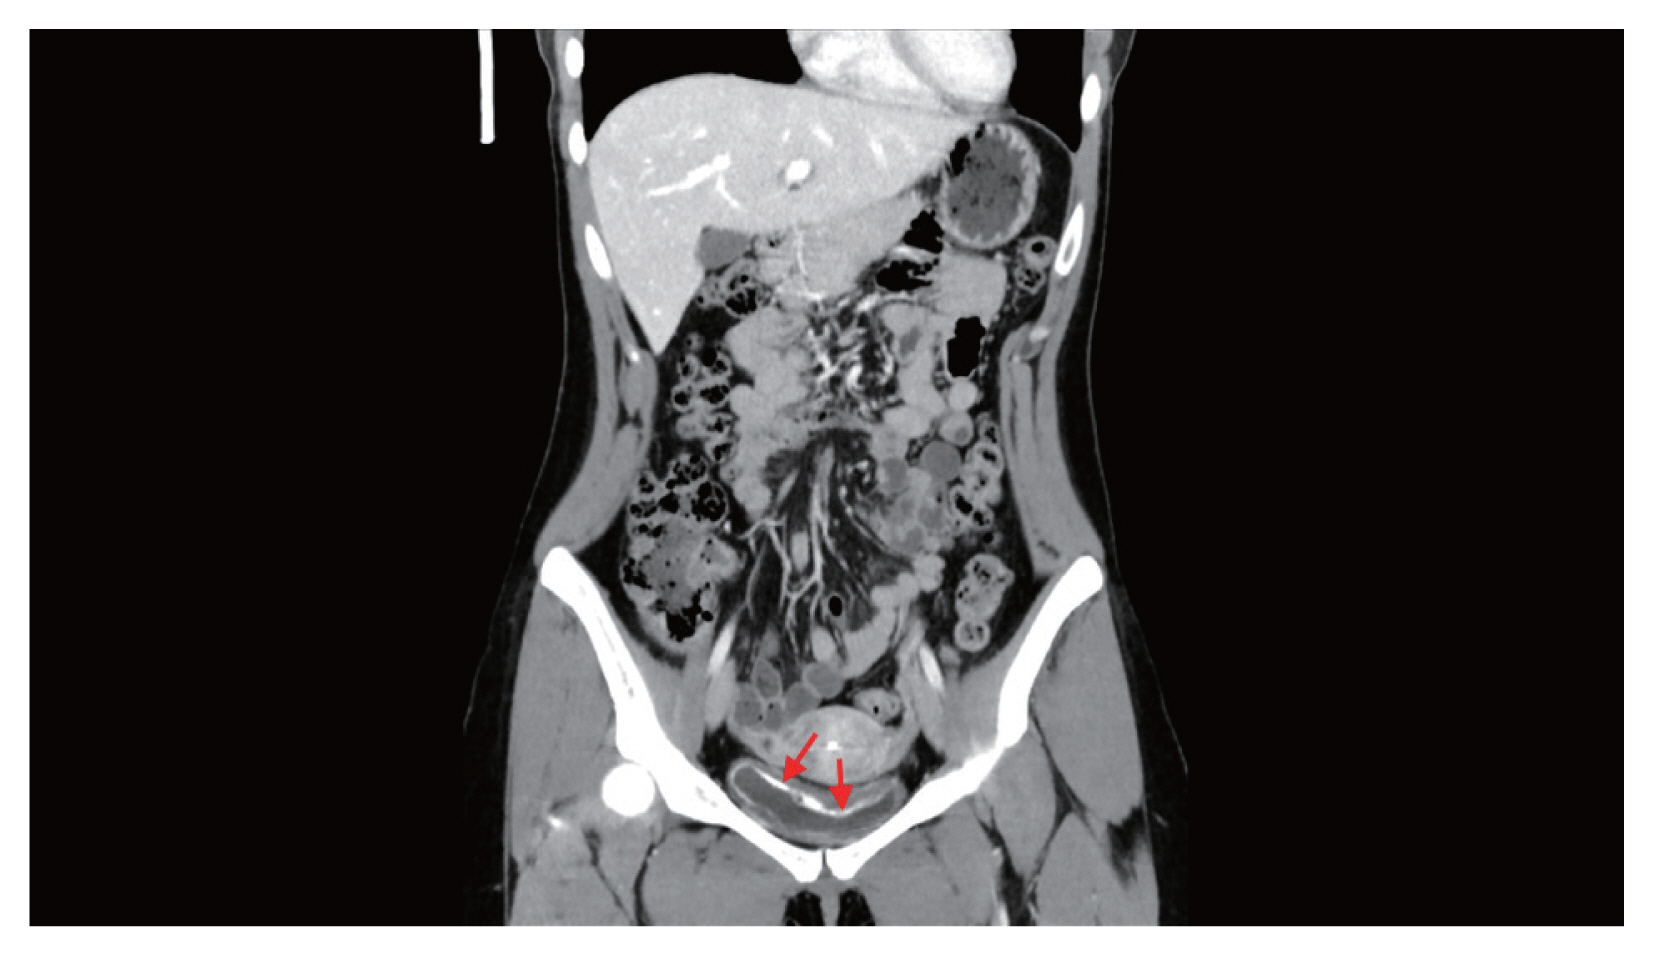

Hematuria had been continued at the time of admission. Urinalysis showed hematuria, proteinuria, and pyuria with a positive nitrite result. In urine cytology, abnormal findings were not identified. Blood tests revealed eosinophilia (1,129/μl, 19.5%) without anemia (hemoglobin 13.2 g/dl). Asymmetrically diffuse mucosal wall thickening and calcification were observed at the urinary bladder on pelvic CT (Fig. 1). Multiple erythematous nodular lesions and hemorrhage at the urinary bladder mucosa were observed in the cystoscopy and transurethral resection was performed for the histopathologic examination for the lesions (Fig. 2).

Fig. 1

Asymmetrical thickening of the mucosal wall with calcification (arrows) at the urinary bladder on pelvic CT.

Fig. 1 Asymmetrical thickening of the mucosal wall with calcification (arrows) at the urinary bladder on pelvic CT.